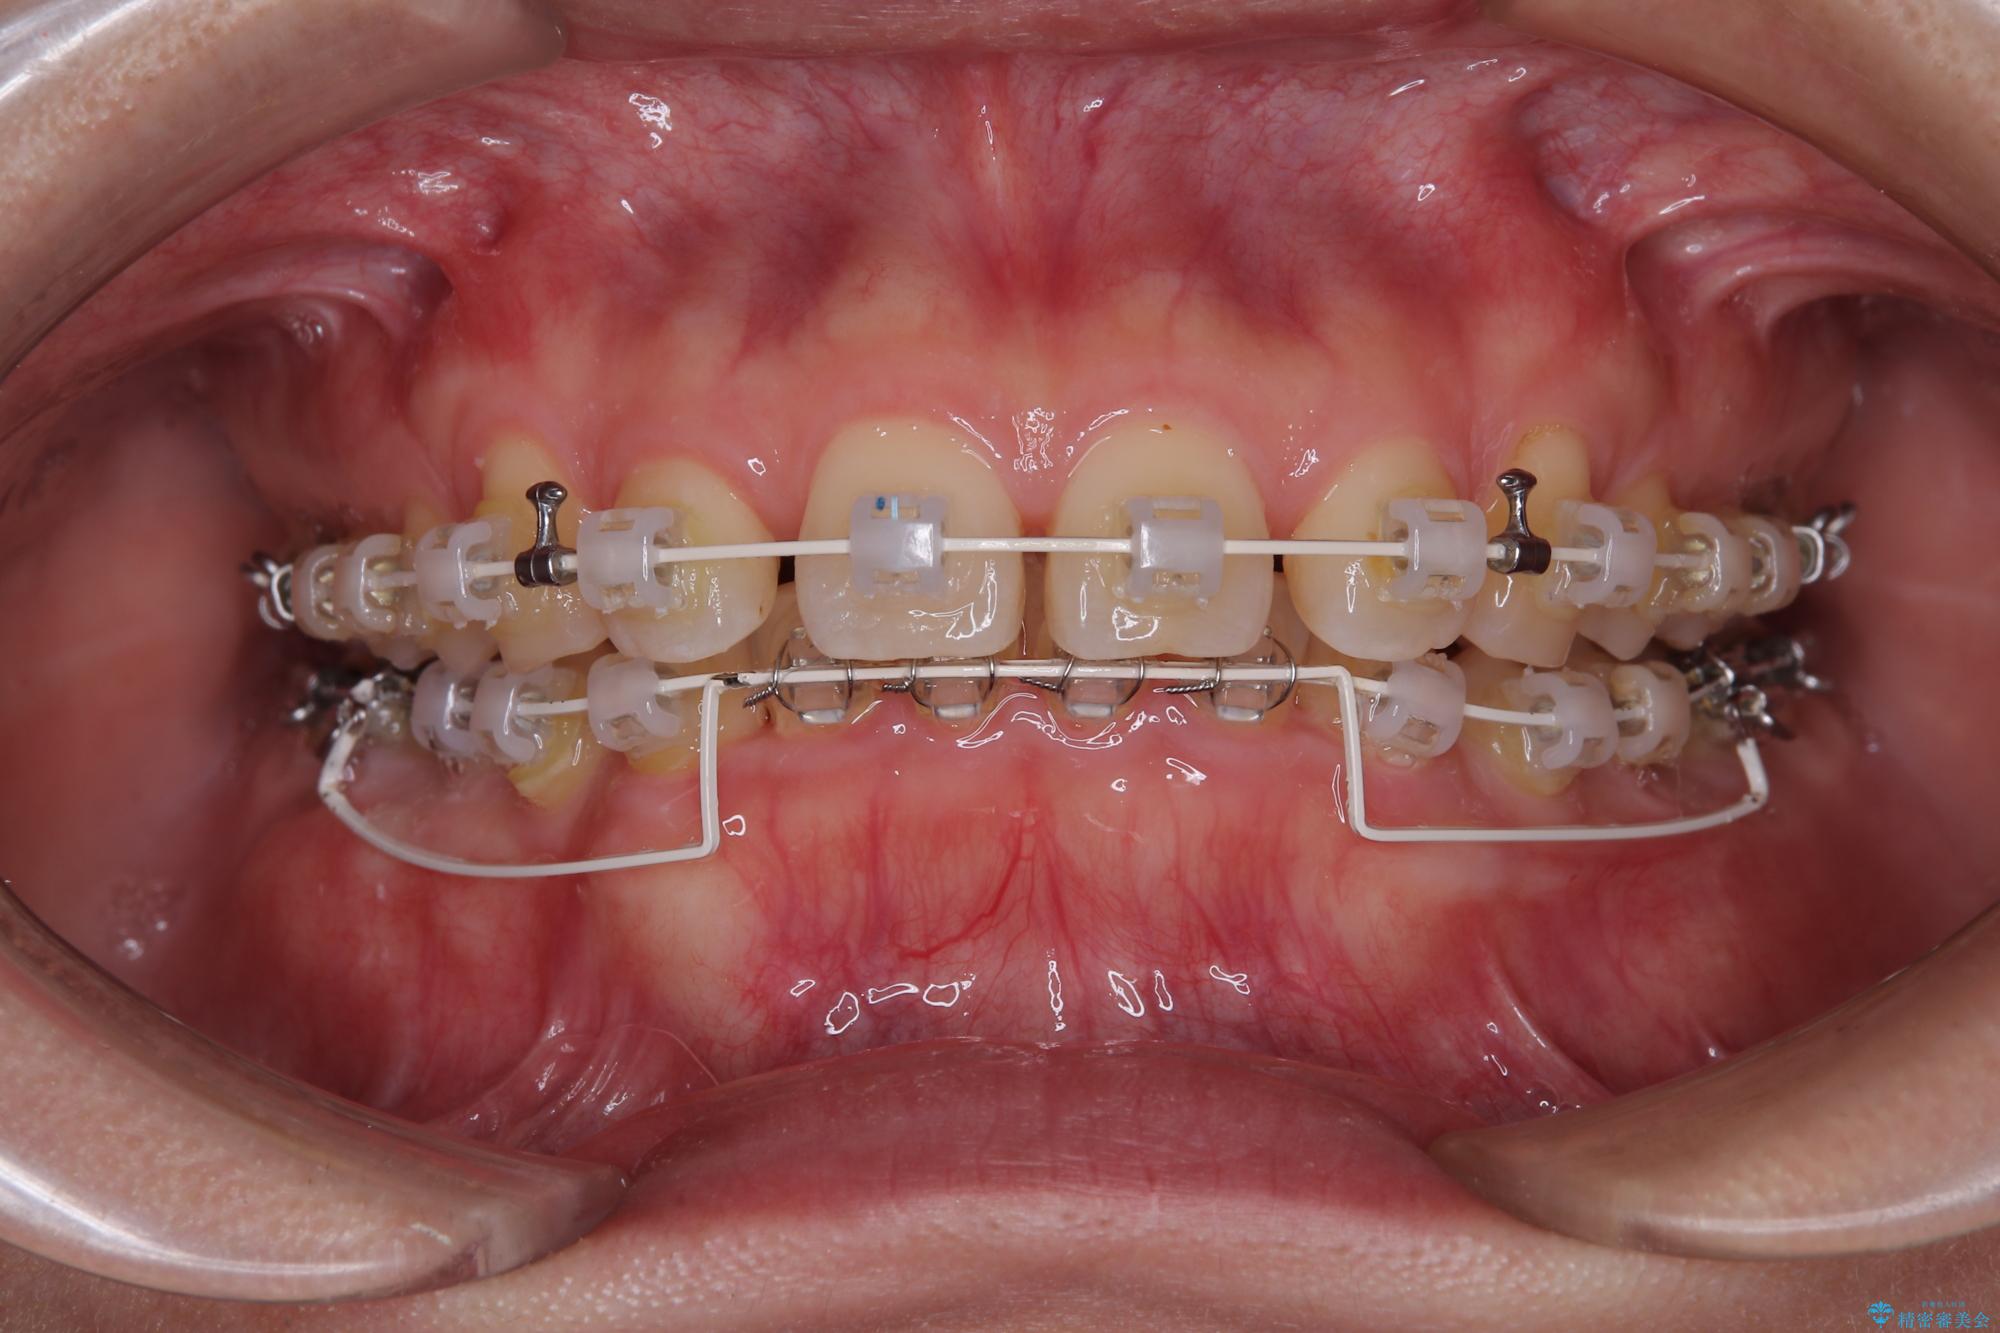

下顎臼歯を起き上がらせるためにユーティリティーアーチを使用し、一気に深い咬み合わせを改善することができました。